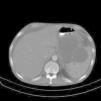

Regarding imaging assessment, abdominal sonography demonstrated ascitis (free fluid in abdomen and pelvic), hypoechoic lesions, calcified lesions and lesions with calcified rim in liver, two similar lesions in pancreas and similar lesions in spleen beside splenomegaly and a 5mm stone and two calcified cyst containing debris in spleen. In chest X-ray (CXR) decreased disk height at T11–T12 level with collapsed T11 vertebral body and paravertebral soft tissue were observed. Abdominal CT showed small sized hypodense lesions in left lobe of liver (Fig. 1), multiple hypodense splenic (Fig. 2) and pancreatic lesions (Fig. 3), left sided pleural effusion, thickening of jejuneal mucosa and edema of bowel wall and ascites (Fig. 4). Vertebral body lesion and paravertebral abscess (Fig. 5), bony calvarial involvement and adjacent extra-axial brain lesion (Fig. 6) are other findings.

Some presentations of extra-pulmonary pnemocystosis are focal low attenuation splenic lesions that becomes progressively calcified; punctuate calcification in the liver, renal cortex and adrenal glands; lymph node calcification, and pleural and peritoneal effusion with subsequent calcification in the surface18 Enlarged heterogeneous spleen with innumerable, low attenuation, hypodense lesions; hepatomegaly; gallbladder wall thickening are some findings reported in extrapulmonary pnemocystosis, as well.15 CXR of our case demonstrated decreased disk height at T11–T12 level with collapsed T11 vertebral body and paravertebral soft tissue. Abdominal CT findings of our case consisted of small sized hypodense lesions in left lobe of liver and multiple hypodense splenic and pancreas lesions, ascitis and left sided pleural effusion, thickening of jejuneal mucosa and edema of bowel wall and ascitis. Vertebral body lesion and paravertebral abscess, bony calvarial involvement and adjacent extra-axial brain lesion are other findings.